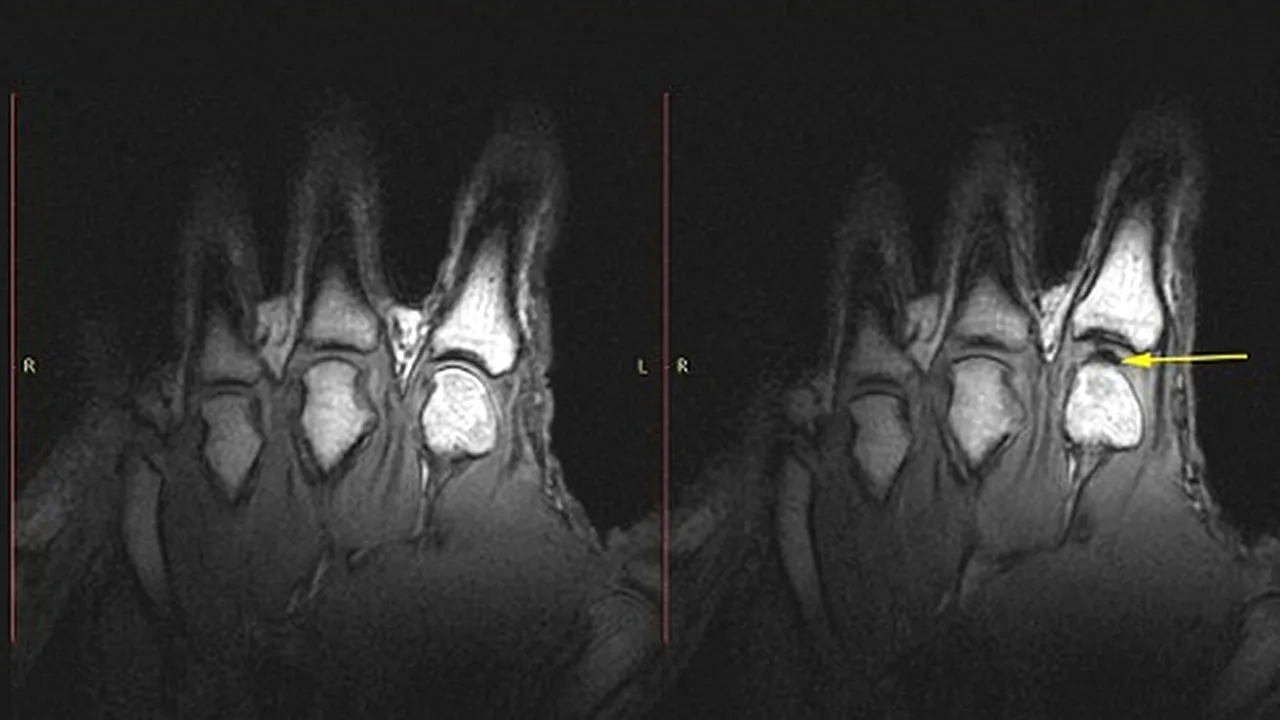

Pe baza unor RMN-uri, canadienii au stabilit că, în momentul în care ne pocnim degetele, articulațiile se îndepărtează ușor, formând o bulă în fluidul dintre ele, iar în acel moment apare și sunetul specific.

„Se formează un fel de vid. Când articulațiile se separă brusc, nu este suficient fluid pentru a umple spațiul format, așa că apare o bulă, iar acest eveniment este asociat cu sunetul respectiv”, a explicat șeful de proiect al cercetării amintite.

Canadienii susțin că trosnirea degetelor este un semn că articulațiile sunt foarte bune și nicidecum cei care își trosnesc degetele nu riscă să facă artrită, așa cum sugerau studii precedente.